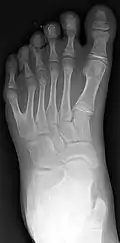

Classification is performed by using x-ray imaging to see the bone structures.[19]

Ulnar polydactyly

The classification of ulnar polydactyly exists of either two or three types. The two-stage classification, according to Temtamy and McKusick, involves type A and B. In type A there is an extra little finger at the metacarpophalangeal joint, or more proximal including the carpometacarpal joint. The little finger can be hypoplastic or fully developed. Type B varies from a nubbin to an extra, non-functional little finger part on a pedicle. According to the three-type classification, type I includes nubbins or floating little fingers, type II includes duplications at the MCPJ, and type III includes duplications of the entire ray.[38]

Radial polydactyly

The Wassel classification is the most widely used classification of radial polydactyly,[7] based upon the most proximal level of skeletal duplication. The most common type is Wassel 4 (about 50% of such duplications) followed by Wassel 2 (20%) and Wassel 6 (12%).[7]

Central polydactyly

The classification of central polydactyly is based on the extent of duplication and involves the following three types: Type I is a central duplication, not attached to the adjacent finger by osseous or ligamentous attachments; it frequently does not include bones, joints, cartilage, or tendons. Type IIA is a nonsyndactylous duplication of a digit or part of a digit with normal components, and articulates with a broad or bifid metacarpal or phalanx. Type IIB is a syndactylous duplication of a digit or part of a digit with normal components, and articulates with a broad or bifid metacarpal or phalanx. Type III is a complete digital duplication, which has a well-formed duplicated metacarpal.[20]